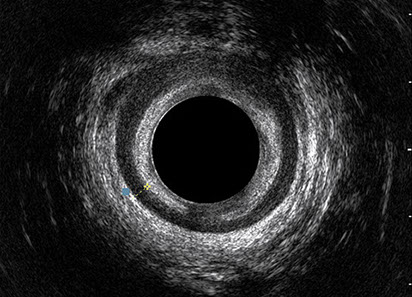

L’ecografia transanale è un esame diagnostico per immagini che consiste nell’introduzione di un trasduttore ad ultrasuoni. Le immagini qualitativamente migliori del canale anale sono ottenute usando un trasduttore rotante, montato in un manipolo rigido, che fornisce un’immagine a 360°. Con le apparecchiature più moderne è anche possibile ottenere immagini tridimensionali.

L’ecografia transanale permette di distinguere la sottomucosa che riveste il canale anale, lo sfintere anale interno, e lo sfintere anale esterno.

Le principali indicazioni all’esecuzione di tale esame sono lo studio dell’integrità delle strutture muscolari nei casi di incontinenza fecale, lo studio topografico dei processi settici perianali (ascessi e fistole) e lo studio dei processi proliferativi epiteliali (carcinoma anale).

Proctal dispone di apparecchiatura per ecografia endoanale 3D con sonda rotante.

Sezione Longitudinale 3D con Tramite Fistoloso Intersfinterico Basso Anteriore Semplice